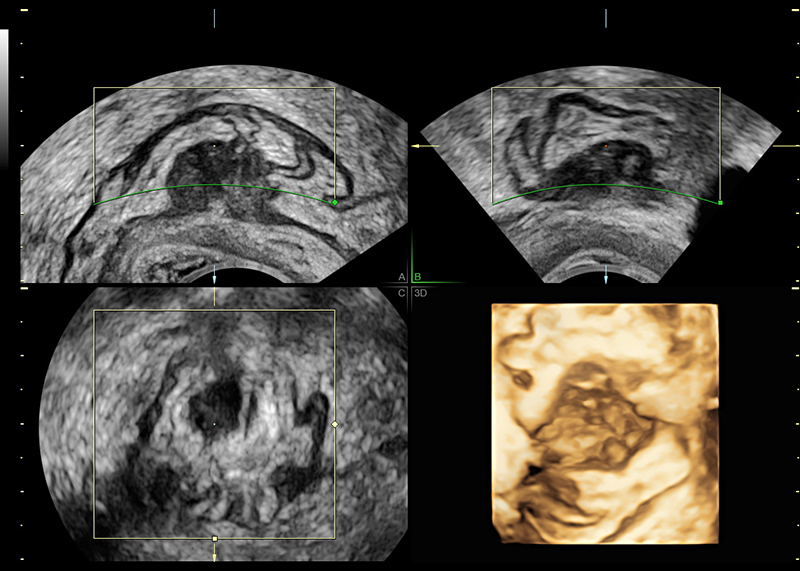

Traditional ultrasounds can miss small or deep infiltrating endometriosis. Advanced gynecological ultrasound, however, combines high-frequency probes, 3D/4D imaging, and specialized Doppler evaluation to provide detailed visualization of the uterus, ovaries, and pelvic structures.

- Ovarian endometriomas (chocolate cysts)

- 3D volumetric scans for a complete anatomical overview